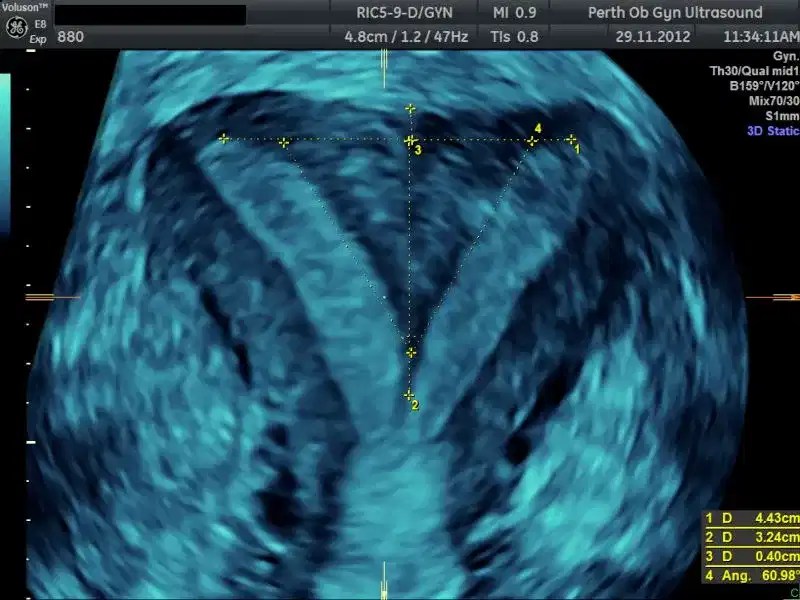

From www.wjgnet.com

Threedimensional imaging of the uterus The value of the coronal plane What Is A 3D Pelvic Ultrasound During an exam, a technologist uses a special probe to take many. A pelvic ultrasound is an imaging test that uses sound waves to make pictures of what's inside your pelvis. It provides detailed views for. What is a pelvic ultrasound? A pelvic ultrasound is a diagnostic exam that produces images—which are called sonograms—of the organs and structures within the. What Is A 3D Pelvic Ultrasound.